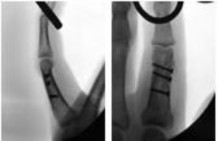

- الأشعة السينية (X-rays): هي الخطوة الأولى في تقييم الكسور، الخلوع، وتغيرات التهاب المفاصل. تساعد في تحديد مدى تدهور العظام والمسافات المفصلية. على سبيل المثال، تُظهر صور الأشعة السينية كسور السلاميات

أو كسور قاعدة العظم المشطي الخامس

، بالإضافة إلى علامات مثل "الدمعة الشعاعية" (Radiographic Teardrop) في الرسغ التي تمثل الزاوية الزندية الراحية الحرجة للكعبرة البعيدة

. - الأشعة المقطعية (CT Scan): توفر صوراً تفصيلية ثلاثية الأبعاد للعظام، وهي مفيدة جداً لتقييم الكسور المعقدة، مثل كسور العظم الخطافي (Hamate Hook Fracture) التي قد لا تظهر في الأشعة السينية العادية